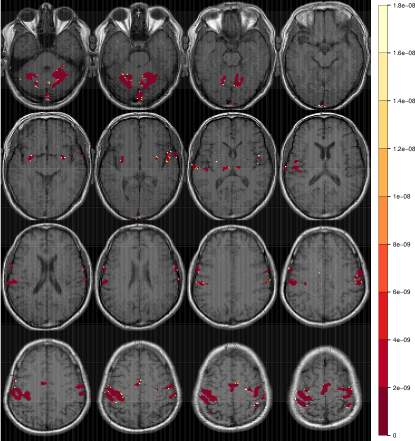

Refer to caption

Figure 2: Radiologic view maps of observed p𝑝p-values of activation of the t𝑡t-test of motor function for (a) the right-hand and (b) left-hand finger-thumb opposition task experiments. For each set of experiments, we display radiologic view maps for the 18th, 19th, 20th and 21st slices (row-wise). The twelve replications are represented column-wise from 1 through 12. For each slice, we display the p𝑝p-values of activation for the thresholded voxels using a t𝑡t-test of the motor function for the twelve replications of the finger-thumb opposition experiment performed by (a) the right hand and (b) the left hand of the same right-hand dominant male volunteer. Note the differences in location and extent of activation over the twelve replications. Note, also the substantial more variability in the experiments performed by the subject’s left hand than on the right.

Figure 2 represents the observed p𝑝p-values of activation for slices 18, 19, 20 and 21 (row-wise) over the twelve replications for both the (a) right-hand and (b) left-hand finger-thumb opposition tasks. (All displayed maps in this paper are in radiologic views and overlaid on top of the corresponding T1fragmentsT1\mbox{T}_{1}-weighted anatomical images.) The specific slices were chosen for display because they encompass the ipsi- and contra-lateral pre-motor cortices (pre-M1), the primary motor cortex (M1), the pre-supplementary motor cortex (pre-SMA), and the supplementary motor cortex (SMA). Clearly, there is some variability in the results for the right-hand task. In Figure 2a for instance, all experiments identify activation in the left M1 and in the ipsi-lateral pre-M1 areas, but there is some modest variability in the identified activation in the contra-lateral pre-M1, pre-SMA and SMA voxels, with some experiments reporting very localized or no activation and others having these regions as activated and somewhat diffused in extent. Slices for the left-hand finger-thumb opposition task experiments in Figure 2b, on the other hand, show far more variability, both in location and extent. It is interesting to note that while most experiments identify activation in the right M1, the ipsi-lateral, contra-lateral pre-M1, pre-SMA and SMA areas, they also often show activation in the corresponding left regions. The case of the eighth replication is extremely peculiar. Most of the activity in the four slices are in the left areas and the right areas have little to no activation. This makes one wonder if the naturally right-hand dominant male volunteer had, perhaps unintentionally and out of habit, used his right hand instead of his left in performing some part of the experimental paradigm. In summary, there is clearly far more variability in the left hand set of experiments than in the right hand set. We now assess the reliability in each set separately.